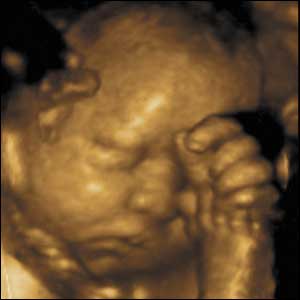

15 týdnů, 11 cm

Mozek pozorovaného dítěte je vyvinutý natolik, že je schopno uvědomit si části svého těla. Může se dotknout prsty tak, že je cítí.